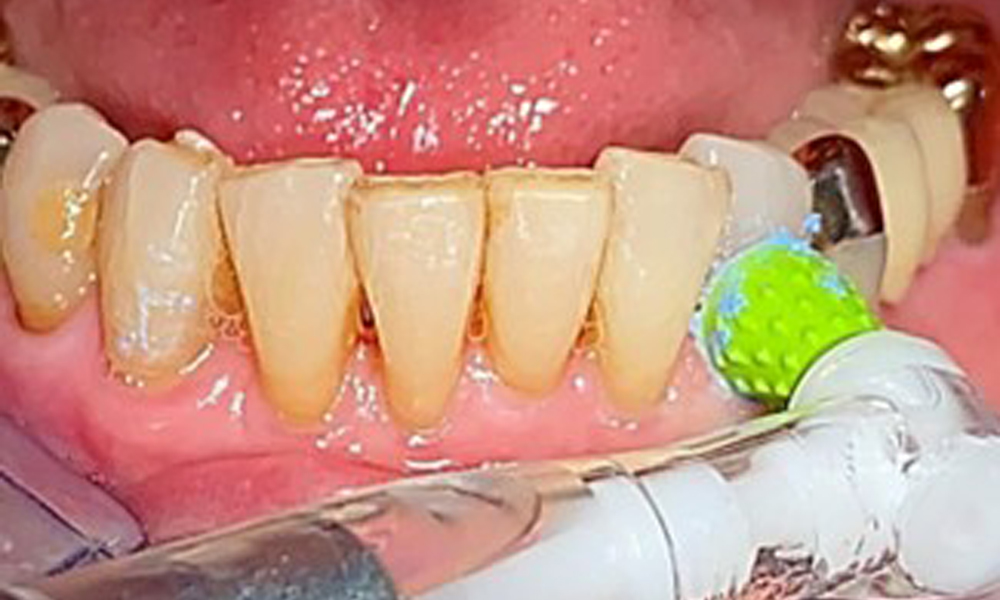

The patient brushes her teeth and implants three times a day with a manual toothbrush and single-tuft brush. She also uses interdental brushes once a day in the evening. She also cleans her prosthesis after every meal.

A single-tufted brush is specifically recommended for the telescopic prostheses (Fig. 8) and the patient should be advised on the appropriate interdental brush size (Fig. 9). The patient has been implementing these recommendations for intraoral hygiene at home for many years and was encouraged to continue during the professional preventive dental appointment.